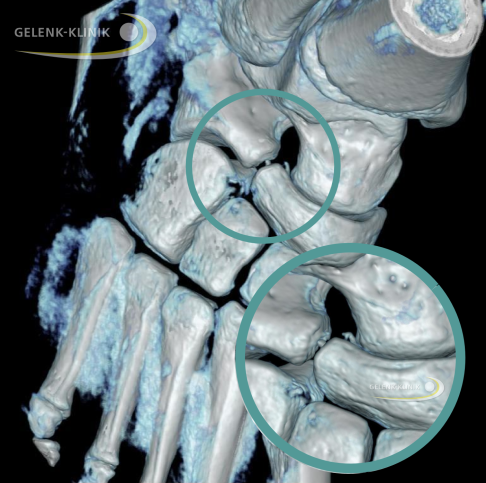

DVT-Darstellung einer partiellen Coalitio mit deutlichen Arthrosezeichen. Rot markiert ist ein knöcherner Kontakt zwischen Sprungbein (Talus) und Fersenbein (Calcaneus). © Gelenk-Klinik

Bleibt die Koalition im Jugendalter ohne Symptome, kann es im Erwachsenenalter zu vorzeitigem Gelenkverschleiß (Arthrose) oder schmerzhaften Bewegungseinschränkungen im betroffenen Fuß kommen. Die Verwachsung zwischen den einzelnen Fußknochen verursacht eine erhöhte Belastung der umliegenden Strukturen. Die gesunden Knorpelflächen der übrigen Rückfuß- und Mittelfußgelenke werden vorzeitig verschlissen, sodass die Betroffenen eine schmerzhafte Arthrose, z. B. subtalare Arthrose oder talonaviculare Arthrose ausbilden können.